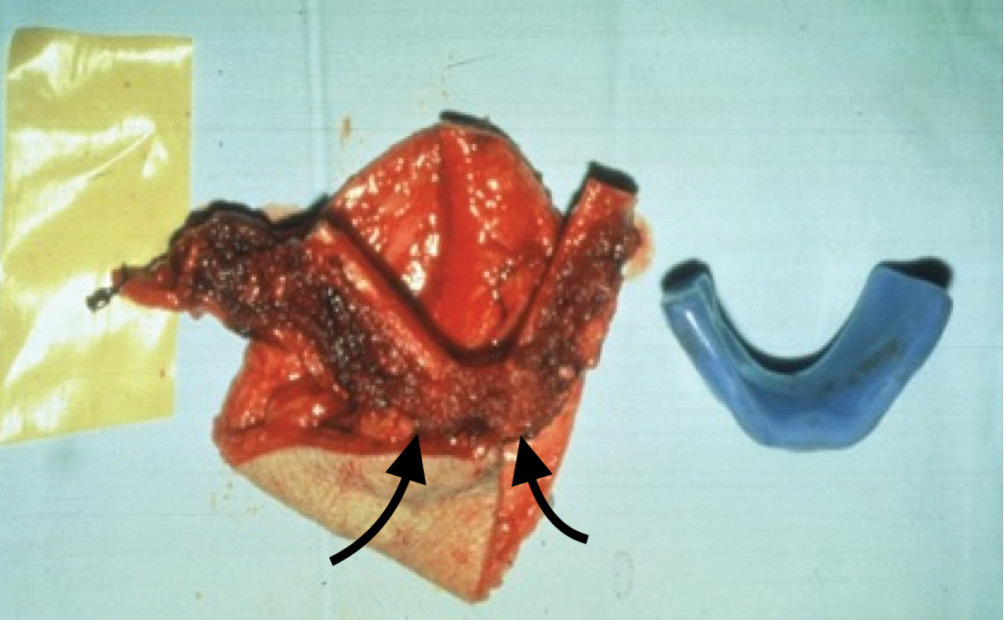

- The jaws: initially we confined the fibula to reconstruction of the bony arch of the mandible or maxilla. A range of acrylic models were used to match the shape of the removed or missing jaw segment shown in Case 5. Two bone wedges were removed from the inner surface of the fibula with an intermediate segment to recreate the chin and fixed with a single mini plate (Figure 24 and Figure 25).